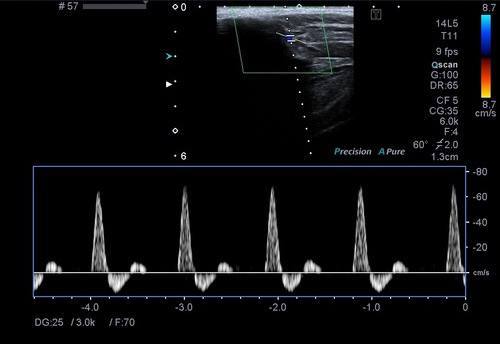

Bu incelemede atardamarlardaki tıkanıklıklar, darlıklar, plaklar değerlendirilir. Damarlardan geçen kanın akım hızları ve debileri ölçülür.

Hipertansiyon, yoğun sigara içiciliği, kolesterol yükseklikleri ve bazı kalp damar hastalıklarında kol ve bacak atardamarlarında damar sertliği bulguları, plaklar veya tıkanıklıklar görülebilir. Bu durumda renkli doppler ultrason ile olası darlıkların dereceleri, plak boyutları, akım hızlarındaki artışlar değerlendirilerek nasıl bir tedavi yapılacağı kararı verilir.